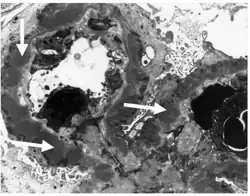

Micrograph of membranous nephropathy showing prominent glomerular basement membrane spikes. Jones' stain.

• By light microscopy, the basement membrane is observed to be diffusely thickened. Using Jones' stain, the GBM appears to have a "spiked" or "holey" appearance.

• On electron microscopy, subepithelial deposits that nestle against the glomerular basement membrane seems to be the cause of the thickening. Also, the podocytes lose their foot processes. As the disease progresses, the deposits will eventually be cleared, leaving cavities in the basement membrane. These cavities will later be filled with basement membrane-like material, and if the disease continues even further, the glomeruli will become sclerosed and finally hyalinized.

• Immunofluorescence microscopy will reveal typical granular deposition of immunoglobulins and complement along the basement membrane.[13]